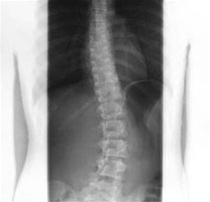

Små skævheder i rygsøjlen er meget almindelige og giver som regel ikke problemer. En skoliose er en skævhed i sideplanet, hvor ryggen - set bagfra - kan have en S-form eller en C-form.

Lægen stiller normalt diagnosen på baggrund af  den kropslige undersøgelse og henviser i visse tilfælde til røntgenbilleder af rygsøjlen.

Den mest enkle metode er at bede barnet/teenageren bøje sig forover. Set bagfra vil man i visse tilfælde se skævheden og en frembuling på den ene side af ryggen.

Forandringerne er oftest i brystdelen af ryggen, men de kan også forekomme i lændedelen eller i overgangen mellem de to områder. Påvises en sådan skævhed af en vis størrelse, så skal barnet have taget et røntgenbillede. Barnet skal som regel også undersøges hos en børnelæge, rygkirurgi eller børneortopædkirurg.